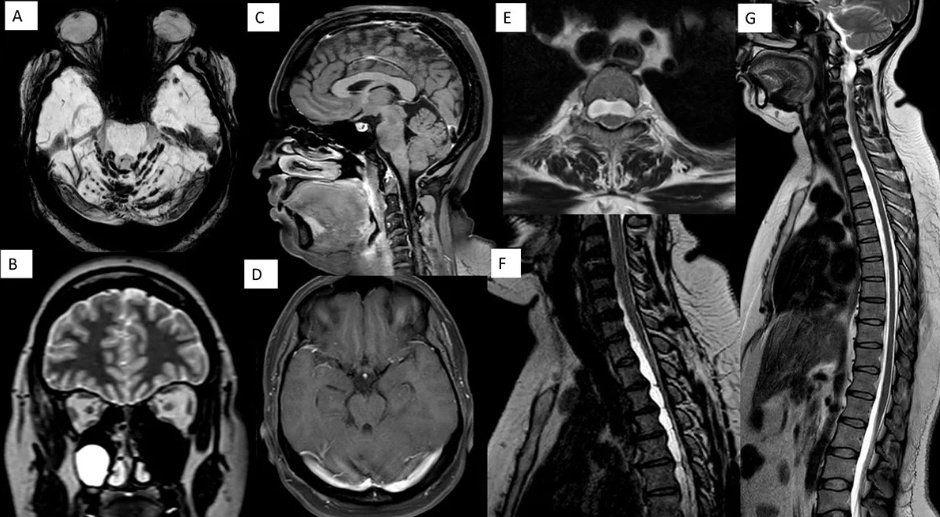

As people of science, the hunger to upskill never really settles — science, medicine, innovation, intervention. Ending 2025 with two ISNR Case of the Month offerings for the ever-curious neuroradiologist 🧠 isnr.in/december-2025-… isnr.in/december-2025-…

♦️ ISNR Case of the month ♦️ isnr.in/july-2025/ Thanks to the contributors Dr Rakesh @DrSmilySharma @drbejoy2002 @ Dr Kesavadas Share your interesting cases @ case.isnr@gmail.com to be featured in the case of the month platform of ISNR website